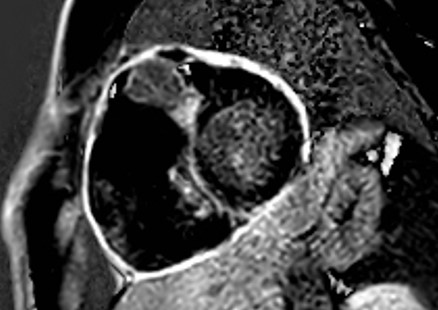

La tomografia computerizzata (TC) total body con contrasto mostrava all'interno del cuore destro una massa ipodensa, solida, che infiltrava le pareti del miocardio (Figura 2), circondava la radice aortica e confluiva nel mediastino superiore in una massa di linfonodi patologici fusi (Figura 3). Per il resto, la TC total body non dimostrava altri siti patologici.

linfoma_cardiaco_2.jpg

Figura 2

La TC permetteva di confermare la malignità della massa, sulla base della sua infiltrazione miocardica e pericardica. Nella fase post-contrasto una scarsa vascolarizzazione del tumore rappresentava una differenza significativa rispetto al tessuto riccamente vascolarizzato dell'angiosarcoma (che è il più frequente tumore cardiaco maligno). Inoltre, la TC evidenziava che il tumore cardiaco continuava nel mediastino superiore in una massa uniforme di linfonodi patologici con lo stesso pattern di segnale. Questo riscontro suggeriva la diagnosi di linfoma. D'altra parte, la mancanza di altre metastasi escludeva la diagnosi di angiosarcoma e di sarcomi in generale.